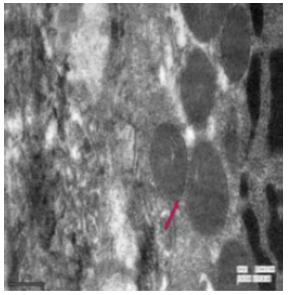

In the duodenum of the control rat, the enterocytes had a regular microvillus border, tiny finger-like projections and a few granular bodies (Figure 47). In the intranuclear region of the enteroendocrine cells, numerous tiny, electron-rich spheroidal granules were present (Figure 48). The microvilli were reduced in height and were damaged (Figure 49). The fluoridated duodenal mucosa had fat droplets suggesting lipid accumulation, vacuolations, a thickened epithelial membrane, multivesicular structures exhibiting endocytic activity and discernible widening of spaces (Figure 50). There were aberrant absorptive cells, granular bodies along mitochondria (Figure 51). The endoplasmic reticulum exhibited vacuolization. Goblet cells were seen among the cellular protrusions (Figure 52). The duodenal mucosa in fluoridated rats appeared flat with the absence of villi, indicating significant damage to the intestinal structure essential for nutrient absorption (Figure 53). Irregular nuclei along with some vacuolation were evident in fluorotic rats. (Figure 54). The jejunum in the control rat revealed normal mitochondria distinctly characterized by its outer membrane and well-developed cristae (Figure 55). Oval basal nuclei surrounded by nuclear membrane were visible in the cells. Several secretory granules and vesicles were present in the cytoplasm (Figure 56). Small intestinal crypts of Lieberkühn included Paneth cells, specialized epithelial cells. The nuclear membrane enclosing the basal nucleus were also seen (Figure 57).

Figure 51: Transmission electron microscopy of duodenum of rat treated with 600 mg sodium fluoride for 40 days showing abnormal granular bodies (↑) along with fragmented mitochondria. X 1100.

Figure 52: Transmission electron micrograph of duodenum of rat treated with 600 mg sodium fluoride for 40 days showing vacuolization of endoplasmic reticulum. Cellular extrusion showing presence of goblet cell was also seen. X 570.

In the fluoride-treated rat, the endoplasmic reticulum had dilated cisternae, contained the virus particles, characterized by an electron-dense core enveloped by one or two membranes (Figure 58). Under the microvilli, a noticeable terminal web was seen and prominent lateral interdigitations were visible between the cells, suggesting complex folding or invaginations of cell membranes. Additionally, the mitochondria appeared swollen with few disintegrated cisternae (Figure 59). The jejunum of fluorotic rats displayed vacuolations. The presence of lysosomes and vesiculated RER was observed in the cytoplasm (Figure 60).

Figure 58: Transmission electron micrograph of jejunum of rat treated with 600 mg fluoride for 40 days showed virus particles (↑) having electron dense core surrounded by one or two membranes. X 5000.

Figure 59: Transmission electron micrograph of jejunum of rat treated with 600 mg fluoride showing interdigitations (↑) swollen mitochondria with few disintegrated cristae. Dilated reR (↑) was also seen. X 2550.

In the ileum of control rat, distinct defensin-rich granules were visible within the Paneth cells, indicating their role in innate immune defence. Furthermore, mitochondria and different secretory granules were also present (Figure 61) and had rough endoplasmic reticulum throughout the cytoplasm (Figure 62). In fluoridated rats, the Golgi apparatus of the ileal tissue appeared aberrant and hypertrophied. The mitochondria had lost their characteristic appearance and were obscured suggesting that high fluoride exposure disrupts cellular structures and functions within the ileum (Figure 63). Significant vacuolations, suggestive of the presence of spaces within the tissue, disintegrated mitochondria and irregularly shaped nuclei were visible (Figure 64). The ileum exhibited irregularities in the rough endoplasmic reticulum (rER) and disruptions in other cytoskeletal components (Figure 65).